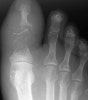

X-ray : 지골 골수염(Phalangeal osteomyelitis)

흔하지 않은 질환으로 조갑감입, 백선증, 당뇨병 합병증이 파급성으로 골수염을 일으키기도 합니다.

혈류가 많은 부위이므로 표저(felon) 등의 감염증을 일으켜도 절개배농으로 치료하지만, 한 번 골수염이 되면 골소파술, 절제가 필요합니다.